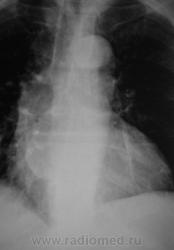

2 срез.

Хорошие томограмы, жаль нет бочка посмотреть вентиляцию нижней доли, а так конечно в просвете бронха дополнительная тень, предсердие бы оттеснило весь бронх. Надо рекомендовать бронхоскопию.